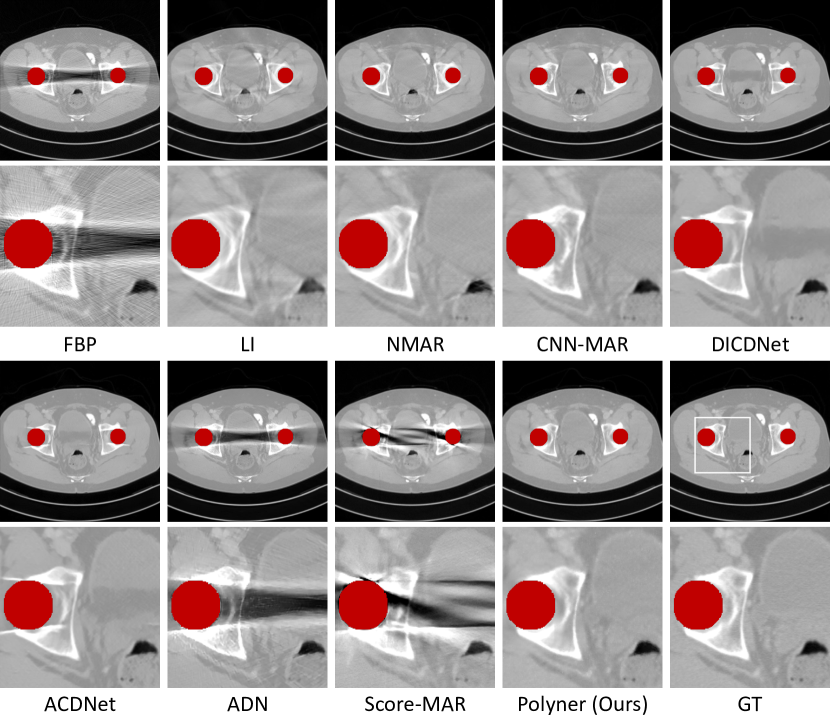

Refer to caption

Figure 3: (Left) A Bruker SKYSCAN 1276 micro-CT scanner and a walnut sample with a metal paper clip. (Right) Qualitative results of the compared methods on the walnut sample data. The red regions denote metals.

Comparison on Real Data. Though our Polyner model performs best on the two simulation datasets, it is important to study its performance on real collected CT data. To achieve this, we insert a metal paper clip into a walnut sample and then scan it with a commercial Bruker SKYSCAN 1276 micro-CT, as shown in Fig 3 (Left). We compare five baselines with our Polyner for reconstructing a 2D slice of the sample. The remaining three baselines (NMAR [11], CNN-MAR [7], and ADN [30]) are not compared because they require prior knowledge of water-bone segmentation, which is invalid for the walnut sample. Fig. 3 (Right) demonstrates the qualitative results. FBP [3] performs the worst, producing severe shadow artifacts. LI [10] exhibits local deformations in the reconstructed images. Score-MAR [9] almost fails due to the domain shift problem. ACDNet [13] is not effective in completely removing these shadow artifacts, it instead produces an offset in image contrast. In comparison, our Polyner recovers the best visual results in both image details and contrast. We also present the quantitative results in Fig. 3. The proposed Polyner achieves the best performance in two metrics. However, it is worth noting that the quantitative performances of all methods are relatively low (the best PSNR of 22 dB by our Polyner) since the reference CT image cannot be considered GT due to the non-negligible non-rigid deformation caused by the metal paper clip insertion. In addition, we compare our Polyner with FDK algorithm [49] on the real mouse tight sample scanned by a 3D cone-beam CT geometry. Related results are provided in the supplementary material.